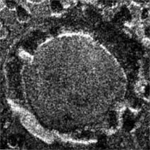

Speckle variance detection of microvasculature using swept-source optical coherence tomography

A. Mariampillai, et al., Optics Letters, 33 (13), 2008.

Link